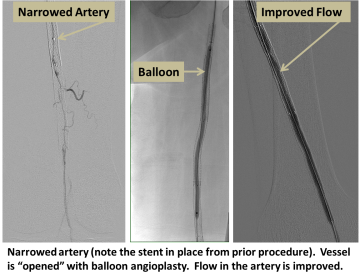

The artery is accessed with a small puncture, and the area of blockage is crossed using specialized wires and catheters. The blockage is then opened using balloon inflation (angioplasty), flexible metallic tubes (stents), or by directly removing the atherosclerotic plaque (atherectomy).